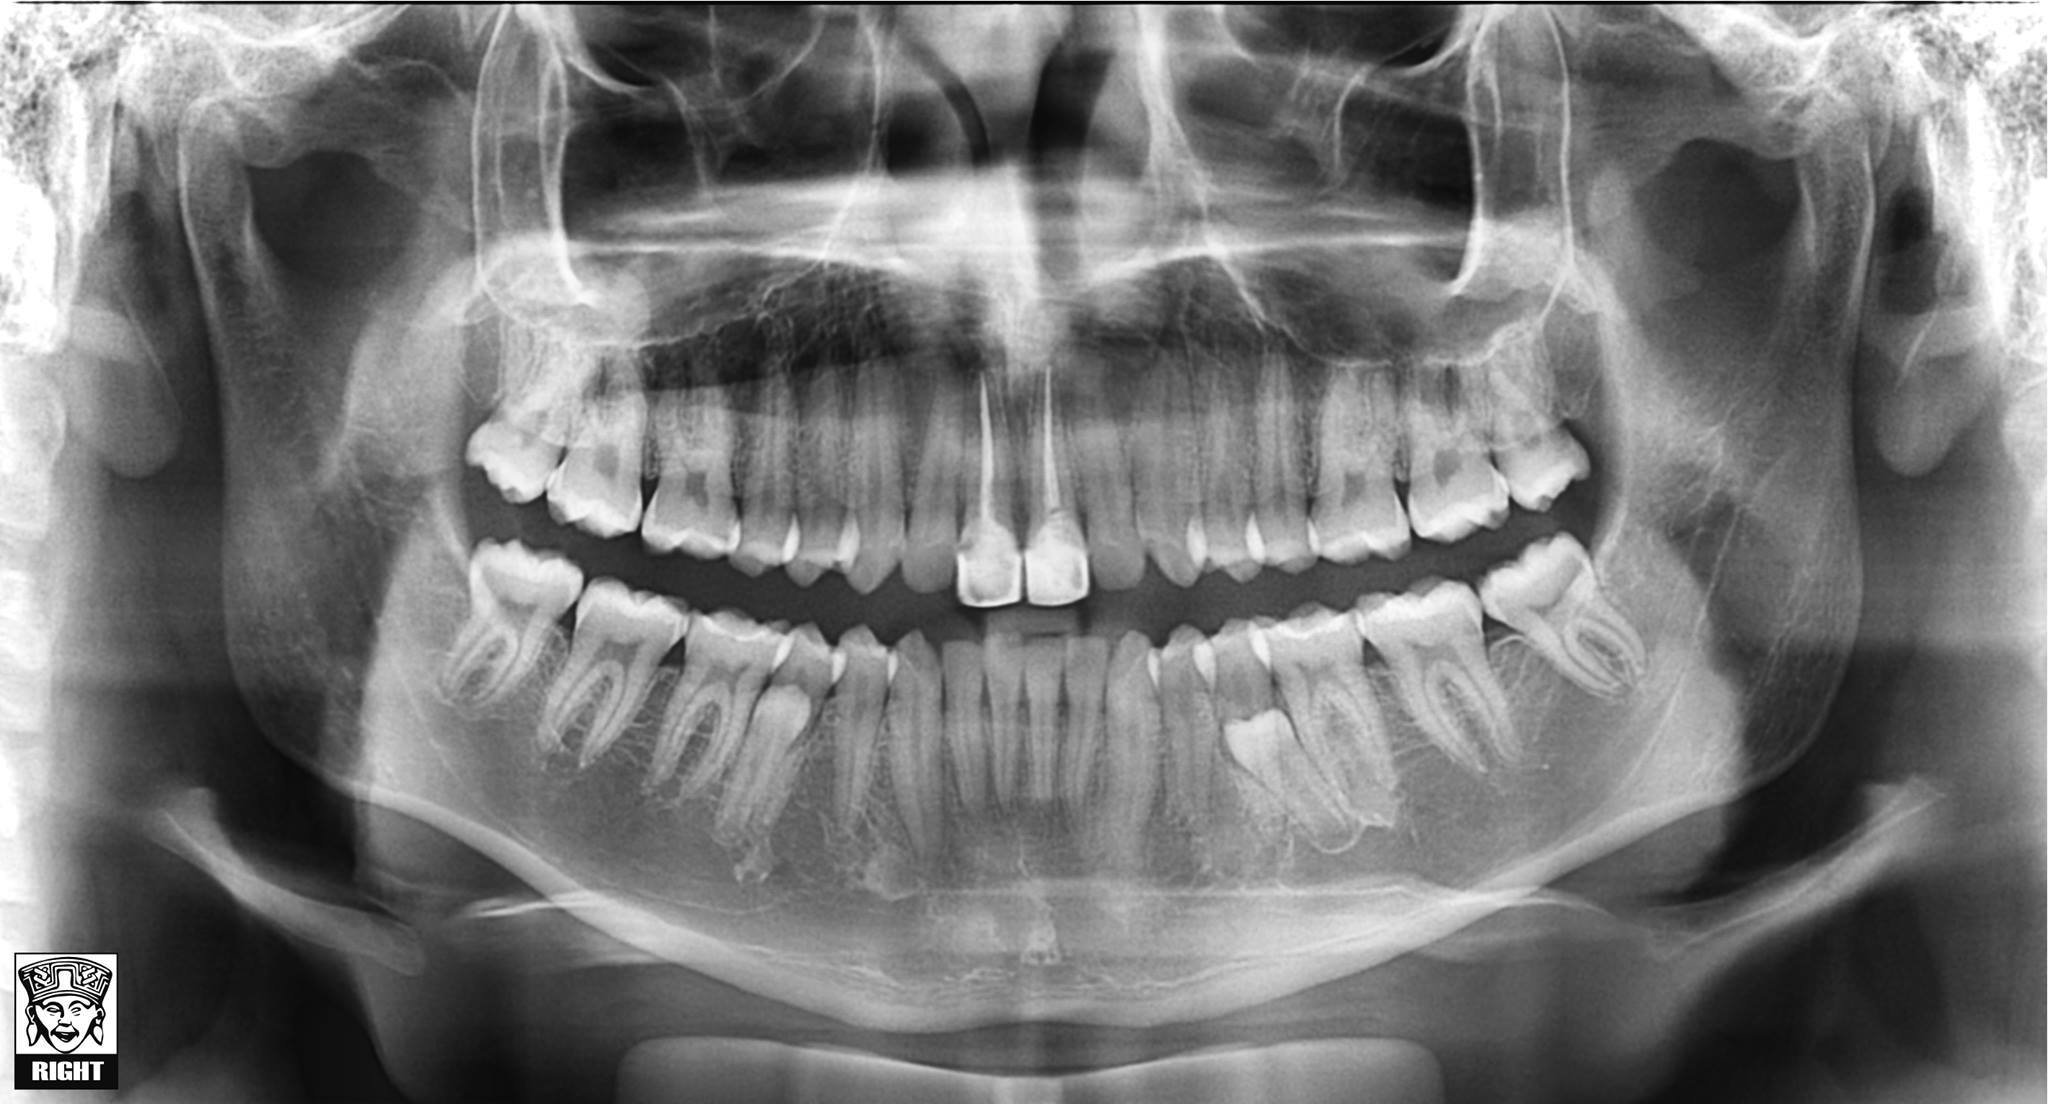

Radiografía Panorámica

Estudio con el que se pueden evaluar, de manera general, las condiciones de tu dentadura y tus huesos maxilares.